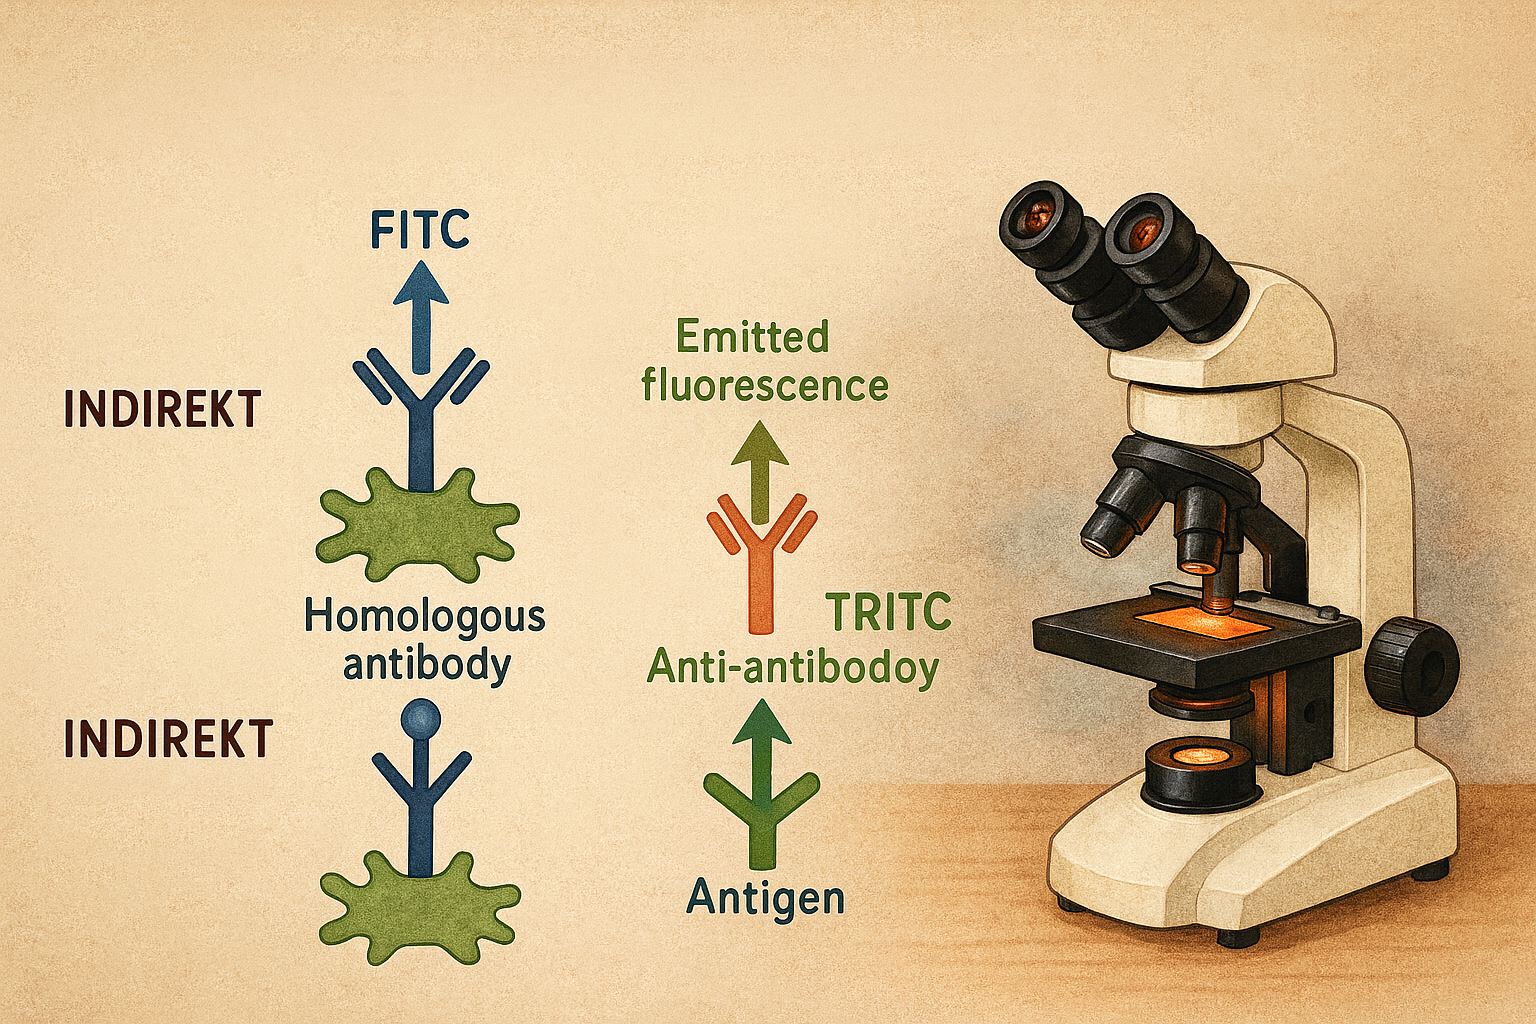

İmmünfloresan testi

İmmünfloresans, özgül antijen–antikor etkileşimini optik olarak görünür kılmak için antikorların bir florofor (flüorokrom) ile kimyasal olarak işaretlenmesine dayanan bir görüntüleme ve tanı yöntemidir. Floroforla konjuge edilen immünoglobulinler, uygun dalga boyunda… Devamını oku